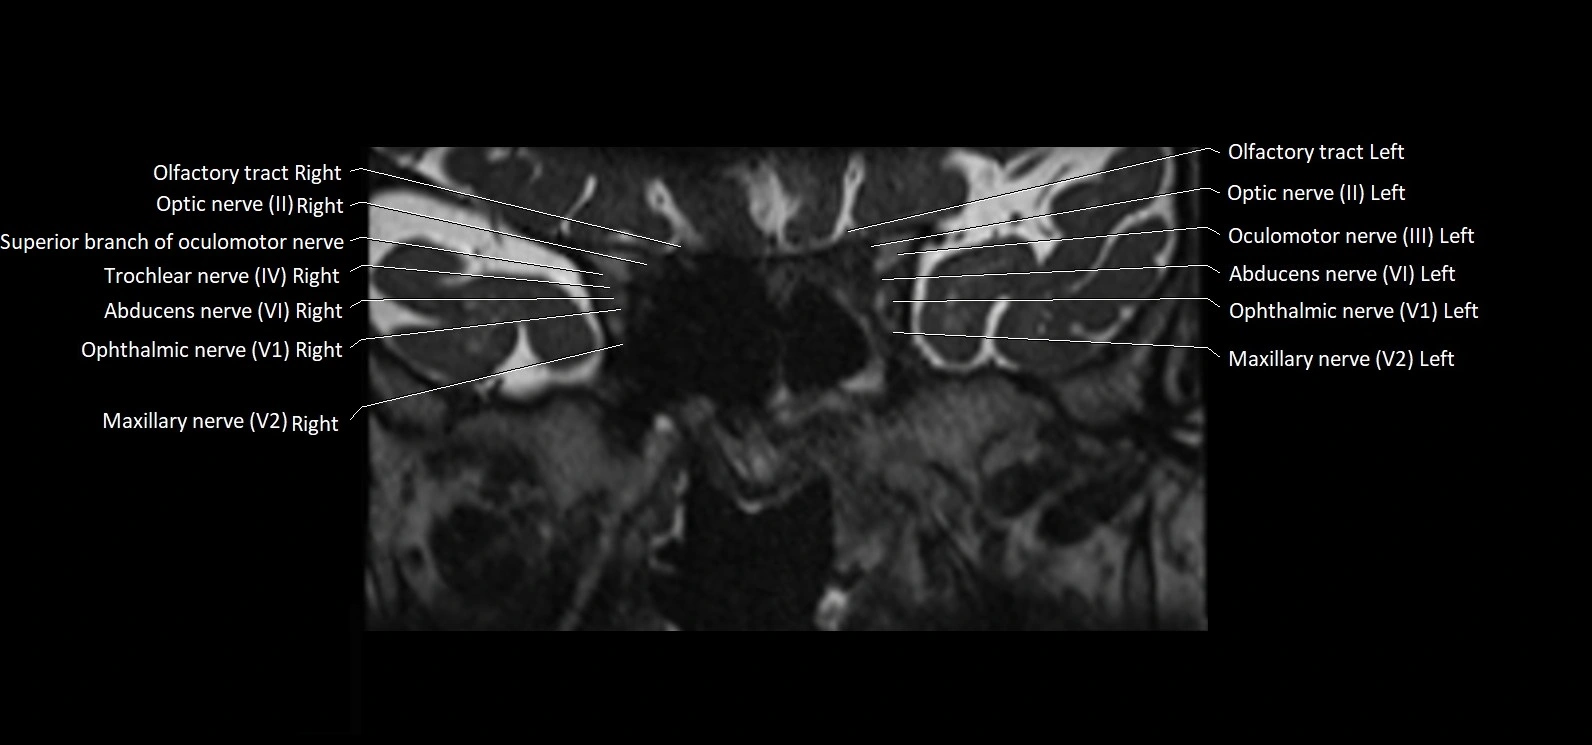

MRI Appearance

• The abducens nerve is a small, thin, linear structure

• Best visualized on high-resolution T2-weighted 3D MRI sequences (e.g., FIESTA or CISS)

• Seen as a hypointense (dark) line running from the brainstem at the pontomedullary junction, traversing the prepontine cistern, and entering Dorello’s canal under the petrosphenoidal ligament, then into the cavernous sinus, and finally the orbit

• May be challenging to visualize in standard MRI due to its small size

• Pathology may be inferred by absence, displacement, or enhancement of the nerve